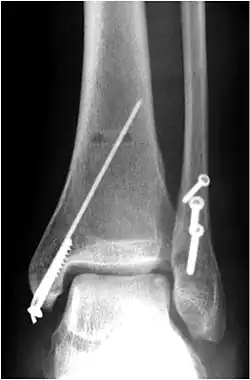

Osteosynthese der Fibula

Sprunggelenkfraktur Weber B, Versorgung des Außenknöchels mit drei Zugschrauben, Innenknöchel mit Zugschraube und Bohrdraht.

Seitliche Projektion der o.a. Osteosynthese

Bei allen anderen Brüchen mit verschobenen Knochenbruchstücken und bei Verletzung der Gabelbänder ist in der Regel eine offene Operation mit Knochenverschraubung (Osteosynthese) und Bandstabilisierung notwendig. Die einfachste und biomechanisch stabilste Versorgung erfolgt mit mindestens zwei bis drei Zugschrauben je nach Länge der Schrägfraktur des Wadenbeins (Abb.). Alleinige Schraubenosteosynthesen sind nur bei einfachen Spiral- oder Schrägbrüchen möglich, Mehrfragmentbrüche werden mit Einzelschrauben zu größeren Fragmenten vereinigt, die dann mit einer Platte stabilisiert werden, die längs auf das Wadenbein verschraubt wird. Im anderen abgebildeten Fall kam eine Zugschraube und eine 6-Loch-1/3-Rohrplatte als sogenannte Neutralisationsplatte am Außenknöchel und eine Zuggurtung am Innenknöchel zum Einsatz. Beide Versorgungen sind übungsstabil, auf eine Gipsruhigstellung kann verzichtet werden. Der Patient darf mit leichter Kontaktbelastung an Unterarmgehstützen gehen.